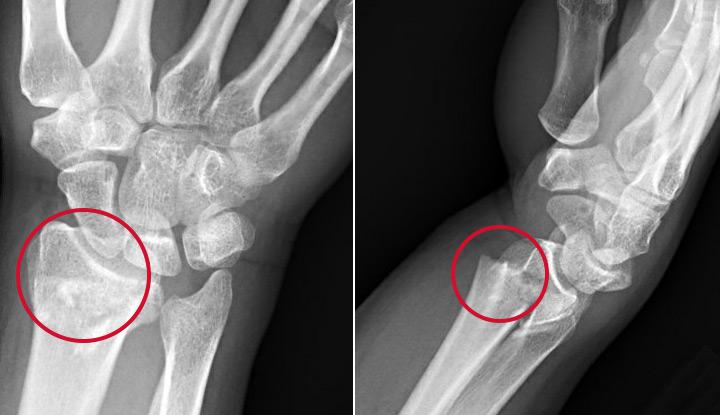

Your healthcare providers at the emergency department will take X-rays of your wrist. The X-rays will show any broken bones.

Colles fractures usually occur after a fall on an outstretched hand. When you reach your hand out to catch yourself in a fall, you might land on the small bones that make up your hand and wrist — especially two bones called the lunate and scaphoid. This contact transfers energy to your radius, one of your two arm bones. The end of the radius near your wrist, called the dorsal end, breaks. This fracture, which typically happens about an inch away from the end of your radius, causes the broken bone to tilt upward.

A Colles fracture is a type of broken wrist (fracture). It’s also called a distal (away from the center of the body) fracture with dorsal angulation (an upward angle). A Colles fracture is a very painful and serious injury. Go to your nearest emergency department if you suspect you have any type of wrist fracture.